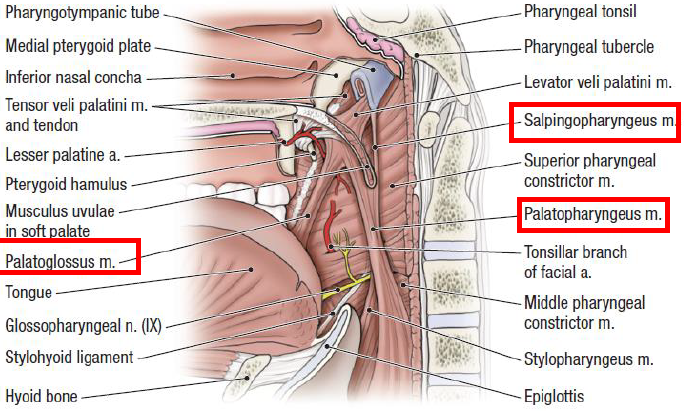

Pharynx

Structure

Nasopharynx

Sensor:CN V

- Opening of Pharyngotympanic tube (auditory tube, Eustachian tube)

- 前:Salpingopalatine fold

- 後:Torus tubarius Salpingopharyngeal fold

- Pharyngeal tonsil

Pharyngotympanic tube

- 通過 Temporal bone

- 後2/3是軟骨

- 通過 Temporal bone

- 後2/3是軟骨

Oropharynx

Sensor:CN IX

由外而內

- Palatoglossal fold(arch)

- Palatine tonsil

- Palatopharyngeal fold(arch)

- 分隔口腔與口咽(fauces)

內部

Vagus 支配

- Palatoglossus m

- palatoglossal fold 下

- Palatine aponeurosis lateral side of tongue

- Palatopharyngeus m

- palatopharyngeus fold下

- Hard palate and palatine aponeurosis Thyroid cartilage and pharyngeal wall

- salpingopharyngeus m.會合

- Salpingopharyngeus m.

- salpingopharyngeal fold下

- Cartilage of pharyngotympanic tube(耳咽管軟骨) thyroid cartilage and pharyngeal wall

- Levator veli palatine m.

- From Scaphoid fossa

V3支配

- Tensor veli palatini m.

- 增加軟顎強度

- 打開耳咽管

- 繞過 pterygoid process